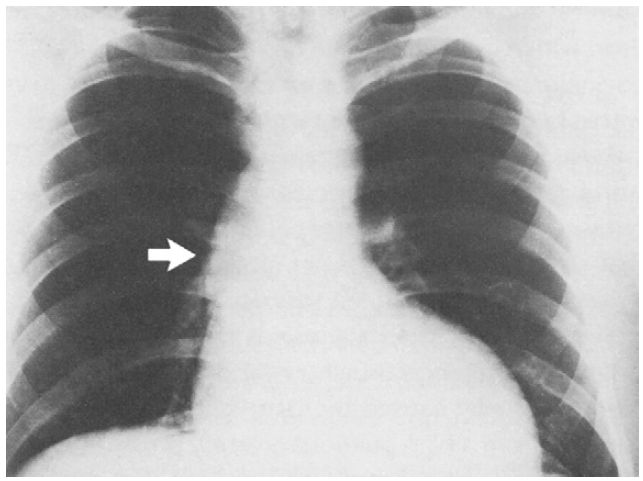

This is the classic ECG appearance of left ventricular hypertrophy. The chest X-ray showed an enlarged left ventricle with ‘post-stenotic’ dilatation of the ascending aorta (arrowed).